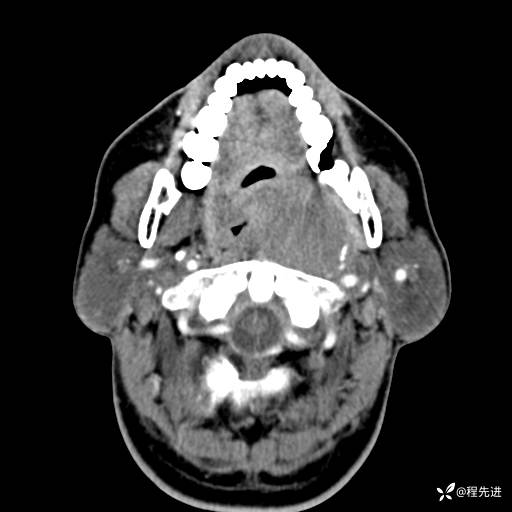

CT平扫:

动脉期: